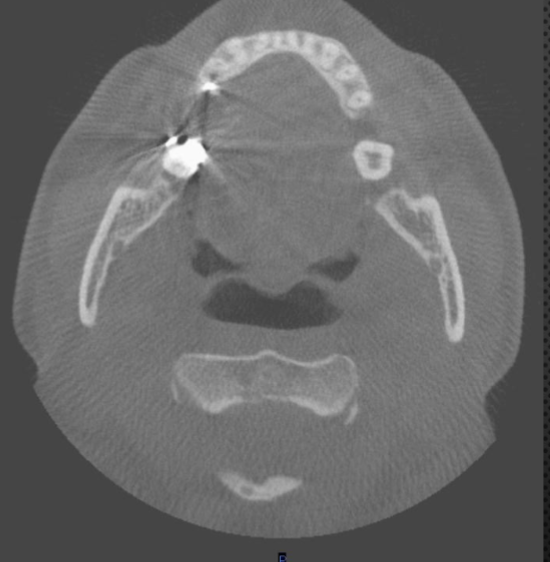

axial

what plane is this

level of maxilla (above maxillary teeth)

at what level is this